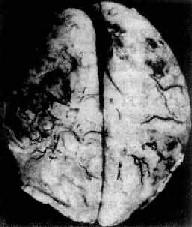

一、细菌性疾病(一)脑膜炎 脑膜炎(meningitis)可累有硬脑膜、蛛网膜和软脑膜。硬脑膜炎(pachymeningitis)多继发于颅骨感染。自从抗生素广泛应用以来,此病之发病率已大为减少。软脑膜炎包括蛛网膜和软脑膜炎症,则颇为常见。因此目前脑膜炎实际上是指软脑膜炎(leptomeningitis)而言。脑膜炎绝大部分由病原体引起,由脑膜炎双球菌引起的流行性脑膜炎是其中最主要的类型;少数则由刺激性化学药品(如普鲁卡因、氨甲蝶呤)引起。脑膜炎有3种基本类型:化脓性脑膜炎,淋巴细胞性脑膜炎(多由病毒引起),慢性脑膜炎(可由结核杆菌、梅毒螺旋体、布氏杆菌及真菌引起)。本节重点叙述化脓性脑膜炎。 1.急性化脓性脑膜炎急性化脓性脑膜炎是软脑膜的急性炎症,大量炎性渗出物积聚于蛛网膜下腔。其中流行性脑膜炎多在冬春季流行,其余病原的脑膜炎则多为散发性。 【病因和发病机制】 急性化脓性脑膜炎的致病菌类型随患者之年龄而异。在青少年患者中以脑膜炎双球菌感染为主。该菌存在于病人和带菌者的鼻咽部,借飞沫经呼吸道传染,细菌进入上呼吸道后,大多数只引起局部炎症,成为健康带菌者;仅小部分机体抵抗力低下的患者,细菌可从上呼吸道粘膜侵入血流,并在血液中繁殖,到达脑脊膜后引起脑膜炎。在冬春季可形成流行,称为流行性脑膜炎。 新生儿脑膜炎最常见的病因是大肠杆菌,感染多来自产道。由于体内缺乏能中和病菌的IgM,入侵的大肠杆菌得以繁殖而致病。 流感杆菌脑膜炎多见于3岁以下之婴幼儿。肺炎球菌脑膜炎在幼儿和老年人常见,其中幼儿的脑膜感染多来自中耳炎,而在老人则常为大叶性肺炎的一种并发症。 【病理变化】 肉眼观,脑脊膜血管高度扩张充血,病变严重的区域,蛛网膜下腔充满灰黄色脓性渗出物,覆盖着脑沟脑回,以致结构模糊不清(图16-10),边缘病变较轻的区域,可见脓性渗出物沿血管分布。在渗出物较少的区域,软脑膜往往略带混浊。脓性渗出物可累及大脑凸面矢状窦附近或脑底部视神经交叉及邻近各池。由于炎性渗出物的阻塞,使脑脊液循环发生障碍,可引起不同程度的脑室扩张。

图16-10 化脓性脑膜炎 蛛网膜下腔内有多量脓液堆积以致大部分脑表面的沟回结构不清;脑膜血管高度扩张充血 镜下,蛛网膜血管高度扩张充血,蛛网膜下腔增宽,其中有大量中性粒细胞及纤维蛋白渗出和少量单核细胞、淋巴细胞浸润(图16-11)。用革兰染色,在细胞内外均可找到致病菌。脑膜及脑室附近脑组织小血管周围可见少量中性粒细胞浸润。病变严重者,动、静脉管壁可受累并进而发生脉管炎和血栓形成,从而导致脑实质的出血性梗死。